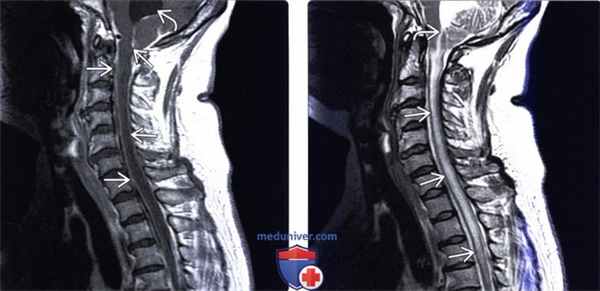

(Слева) Сагиттальный срез, Т1 -ВИ с КУ: распространенное контрастное усиление сигнала мягких мозговых оболочек спинного мозга. Также отмечается расширение четвертого желудочка мозга, связанное в данном случае с кокциодиомикозным менингитом.

(Справа) Диффузная гиперинтенсивность Т2-сигнала на фоне тяжелого кокцидиомикоз но го менингита распространяется от заслонки четвертого желудочка мозга до уровня Т4. Периферия спинного мозга выглядит относительно сохранной. Распространенный отек спинного мозга (предкистозный) обусловлен выраженной гидроцефалией и обструкцией оттока ликвора из полости четвертого желудочка.